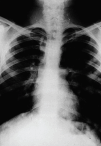

En este momento de la lesión, existen también en la placa anteroposterior de tórax (fig. 3) múltiples imágenes nodulares, fundamentalmente en pulmón izquierdo, indicativas de metástasis pulmonares y que parecen tener una alta densidad sugerente de osificación de las mismas, pues se trataría de células de la misma estirpe ósea que las del tumor primario.